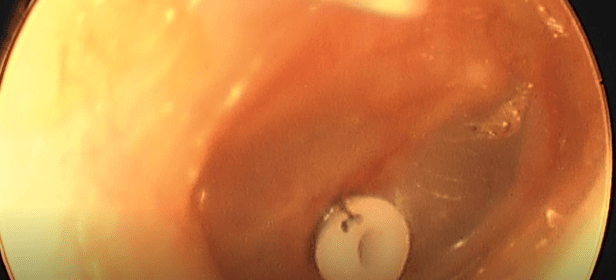

Kulak Tüpü ve Geniz Eti Ameliyatı hakkında bir makale: Avustralya’dan yapılan ve Laryngoscope dergisi Mart 2007 sayısında yayınlanan, 50000’den fazla çocukta yapılan kulak tüpü tatbiki prosedürlerini değerlendiren bir çalışmaya göre, kulak tüpü uygulanması sırasında adenoidektomi (geniz eti ameliyatı) yapılması, tekrar kulak tüpü uygulaması gerekliliğini azaltmaktadır.